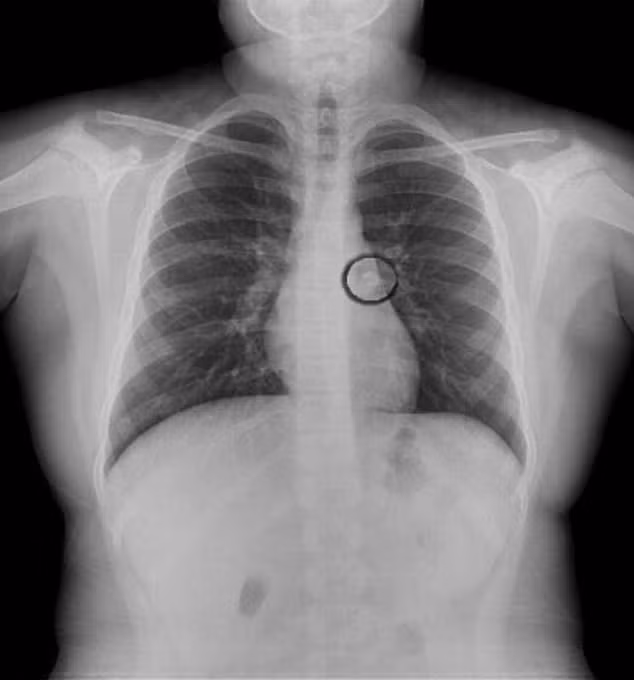

Ảnh X-quang ngực bé gái cho thấy chiếc răng ở trong cơ thể.

Chỉ tới khi được bác sĩ kiểm tra sơ bộ mới có thể nhận thấy phổi trái hoạt động không bình thường và tiến hành chụp X-quang ngực. Chiếc răng sau đó đã được lấy ra khỏi cơ thể bé gái.